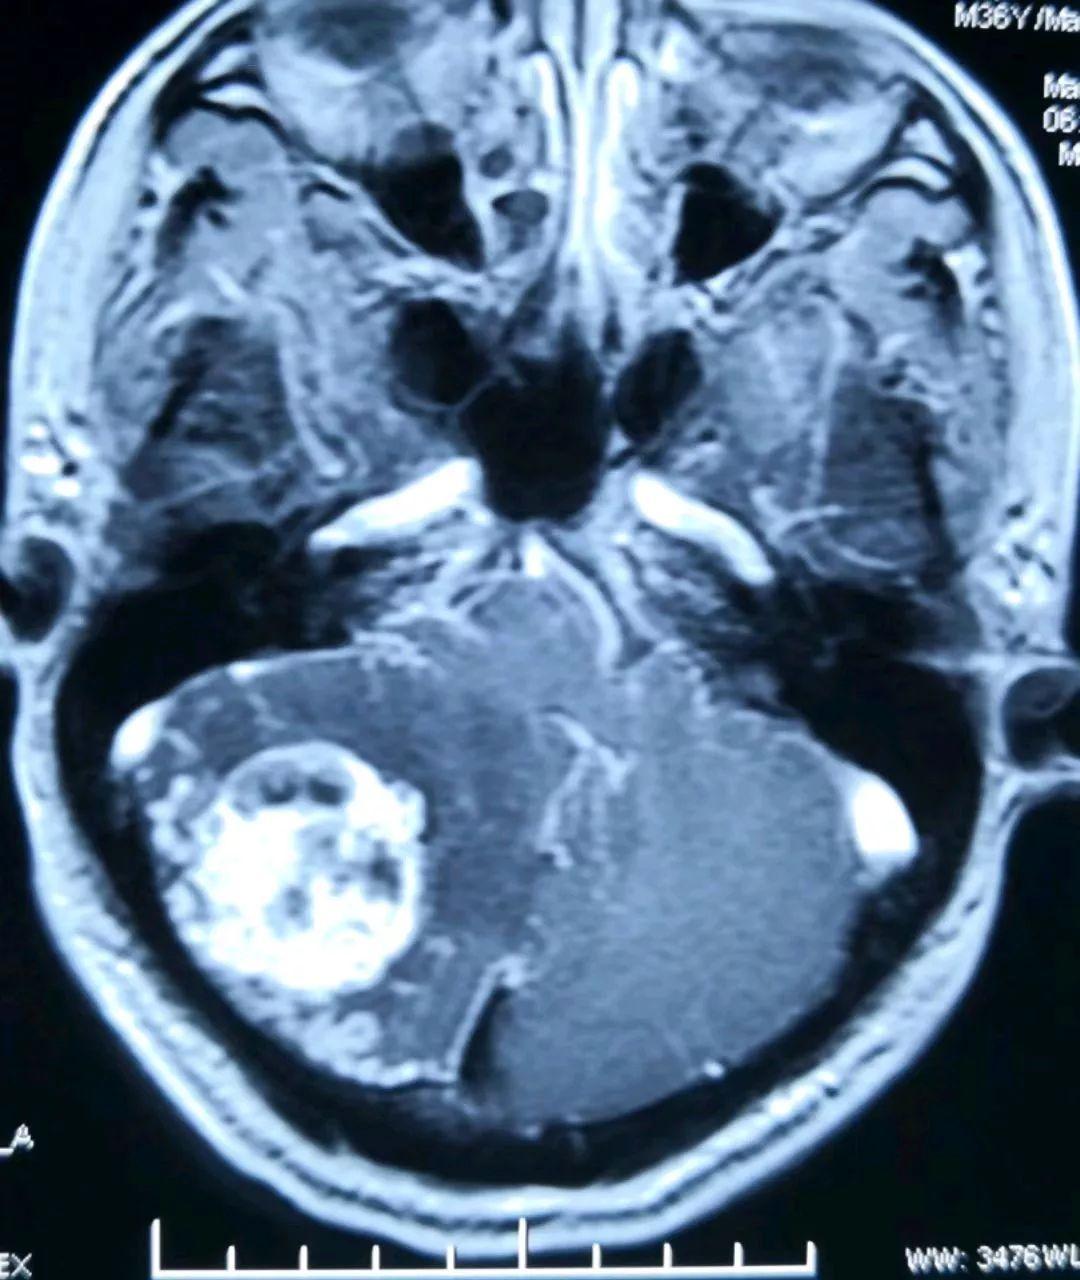

另一位置的增强磁共振提示肿瘤长向小脑深部,靠近脑干组织(人的生命中枢)